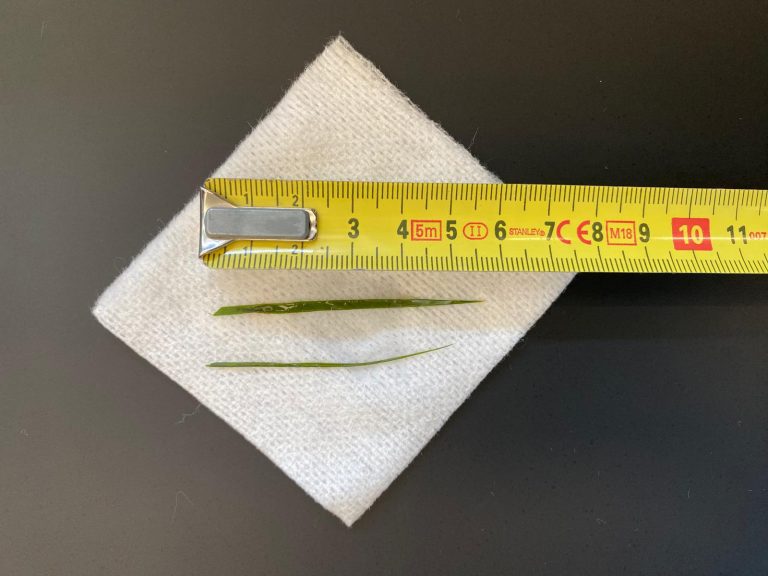

De grote verassing kwam met het feit dat het niet om een verzameling van kleine steentjes ging, zoals meestal. In dit geval ging het om één hele grote steen en meerdere kleinere.

De stenen zijn onderzocht en Spike moest op een dieet blijven staan om de kans op terugkeren van de steentjes zo klein mogelijk te houden.